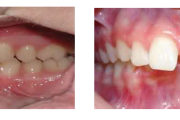

Vali sind huvitav pilt ja me näitame sellega seotud haigust ja sümptomeid